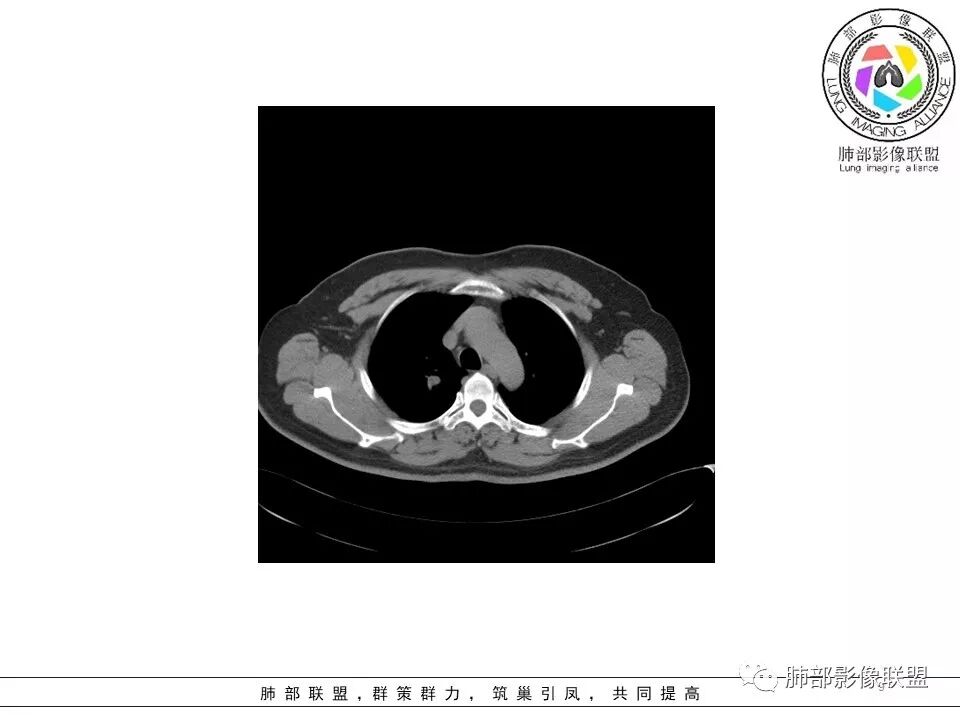

病史:男性,49岁,反复咳嗽月余,伴左胸痛;   影像:形态奇特,长毛刺,疑多灶,支气管阻塞不明显,毛刺不明显,纵膈窗密度不均,其内似见低密度,有凹陷,膨隆不除外,纵膈窗胸膜有点增厚。诊断:结核(右上肺)鉴别:不符合,无钙化,无胸腔积液;腺癌(无淋巴结)。处置:寻找结核相关检查,肿标,纤支镜,增强。

患者中年男性,主诉:咳嗽  胸痛。  胸CT:右肺上叶尖段占位,病灶位于支气管外,病灶周围部分区域可见毛玻璃影,病灶边缘不规则,部分区域可见平直,胸膜牵拉(无胸膜凹陷),柔软长毛刺,分叶,纵隔窗病灶没可见低密度区,左肺尖可见一点状病灶,病灶整体考虑良性疾病:感染性病变(结核?),感染后机化?。恶性病变待除外。

纵隔窗提示内侧部分密度不够实

边缘平直、凹陷为主,部分膨隆

内部小点状影提示可能支气管腔内粘液栓

1、病灶整体形态不是类圆形,边缘凹陷、平直为主,长轴重建可能更明显,长索条,附近卫星灶,左肺尖有类似小高密度影;按常规:首先要考虑结核

南边:2、不踏实的地方:GGO是不是容积效应所致?如果薄层,边界清楚GGO,就考虑继发瘢痕癌